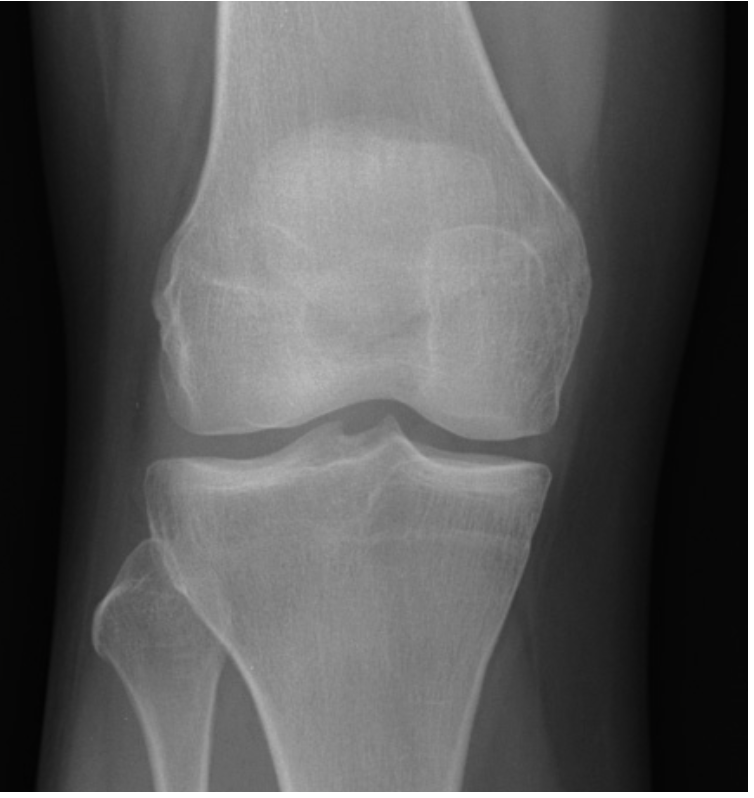

Describe the fracture seen in this X-ray [1]

Lateral tibial plateau fracture

* The fracture fragment is displaced and depressed from its normal position (dotted line)